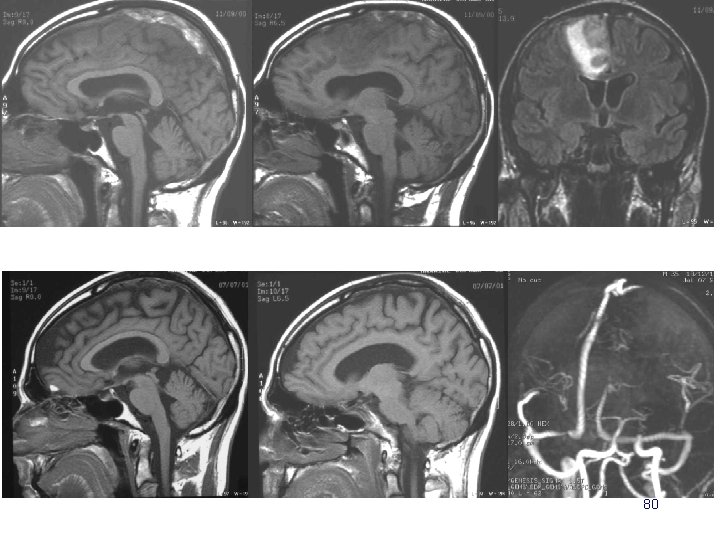

20 ans coma d’installation rapidement progressive 84

6 mois plus tard… mais la patiente se plaint d’acouphènes. Que faut il évoquer? Que proposer? 85

86

87